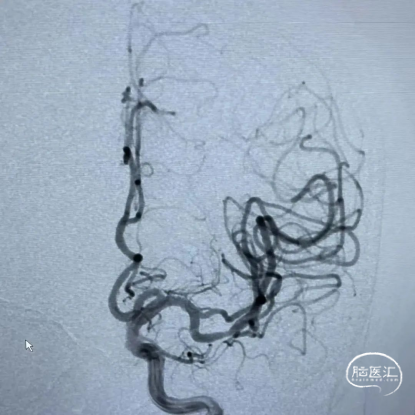

造影示:左侧大脑中动脉M2段管腔纤细、重度狭窄,测量狭窄约80%左右,远端血流缓慢,未见动脉瘤及血管畸形,拟行左侧大脑中动脉M2狭窄段球囊扩张开通支架植入成型术。

患者血管弹性差,拟支架置入术,撤出微导丝,通过21系列 Fastunnel®输送型球囊扩张导管释放自膨式闭环支架完全覆盖狭窄血管,退出Fastunnel®,再次造影见颅内血流较术前有所改善,脑循环时间好转。遂结束手术,拔出动脉鞘压迫15分钟后加压包扎。

术后影像

术后复查头肺部CT,控制性降压,抗血小板、神经营养,对症支持治疗,继续观察。